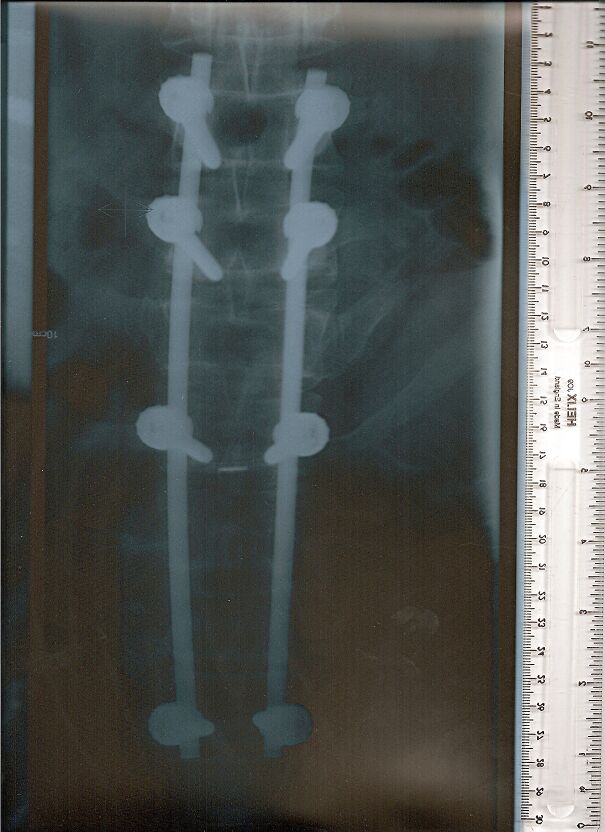

An X-ray showing Robbie Knievel’s spine and an actual photograph of the metal device after he passed away in January 2023.